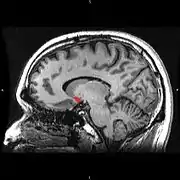

![]() Сагітальна проекція |

| Прилегле ядро на МРТ мозку людини (позачене червоним) |